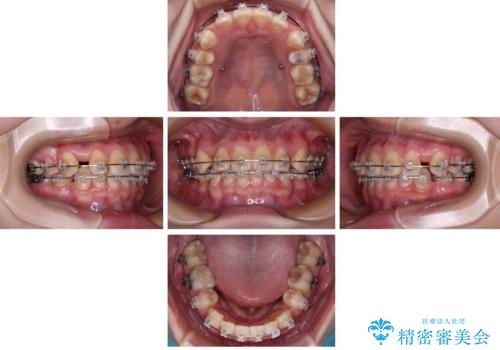

- 矯正装置

- クリアブラケット

- 転勤により東京へ移られることになり転院先を探されていた患者様です。ワイヤー矯正の途中での急な転勤なうえ、今後2~3年以内に再度転勤になる可能性もあるというご事情でした。

そのため、限られた期間内に効率よく治療を完了するために、「抜歯スペースの確実な閉鎖」「深い噛み合わせ(過蓋咬合)の改善」の2点を主軸とした治療計画を立てました。